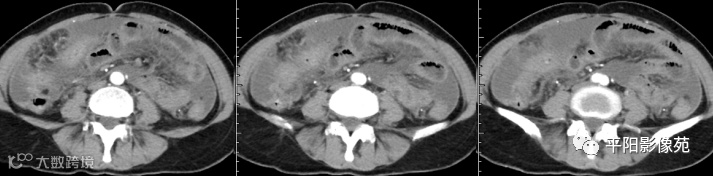

腹部增强 门脉期